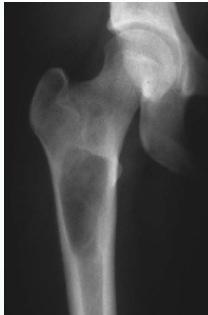

Osteoid Osteoma

- Small tumor (<1 cm)

- Young adults

- Pain, pain, pain:

- Typically relieved by Salicylates

- Sites: Femur, tibia, spine

- X-ray:

- Small radiolucent “nidus”

- Surrounded by sclerotic bone

- CT: Shows “nidus” better

- scan: hot

- Treatment: surgical excision, or thermal ablation

Clinical Example

- 11 year old boy: Pain in left hip